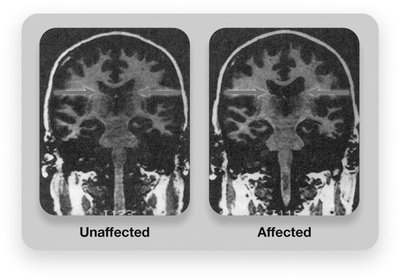

Brain Structure: Larger ventricles, loss of brain tissue, and differences in the hippocampus and amygdala.

Brain Activity: Reduced activity in the frontal lobes and emotion/memory regions.